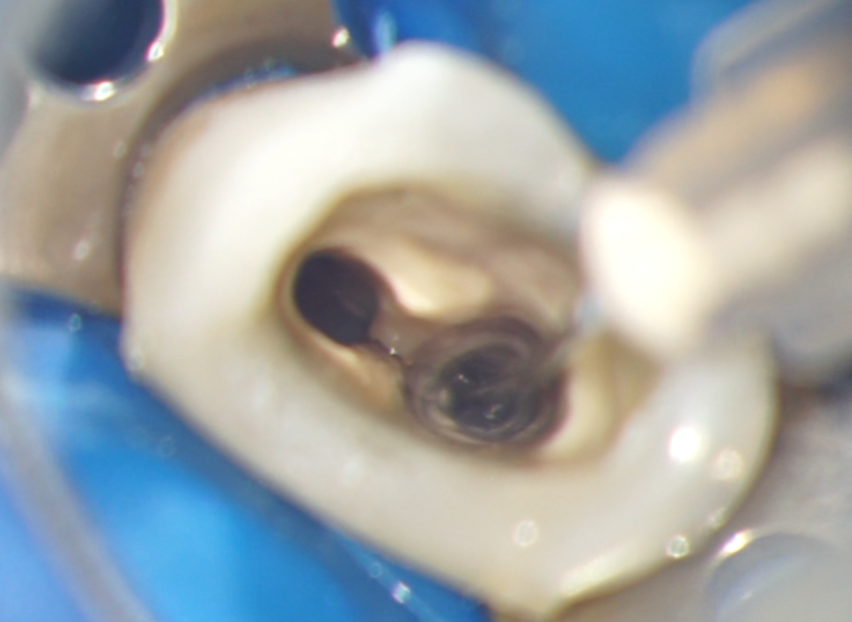

Cel mai utilizat irigant din endodonție este hipocloritul de sodiu (NaOCl). Este singura soluție folosită în prezent care poate dizolva materia organică din canal. El este utilizat în concentrații cuprinse între 0,5-6%. Pentru a maximiza eficacitatea irigării cu hipoclorit în canal (Fig. 4.9.1), soluția trebuie reîmprospătată și păstrată în mișcare prin agitație sau irigare continuă. Viteza de dizolvare a țesuturilor poate fi crescută cu agitație eficientă și împrospătare.